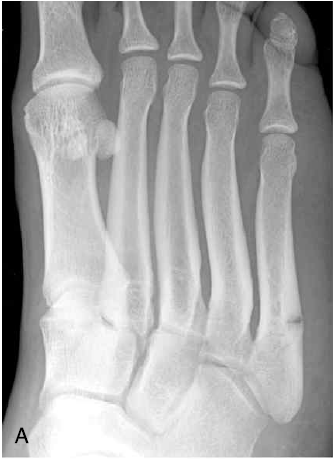

23. 다음 골절에 해당하는 내용과 방사선 사진과 연결시켜라.

A는 존스 골절(Jones fracture). 제5중족골의 기저부의 횡단 골절에 해당한다.